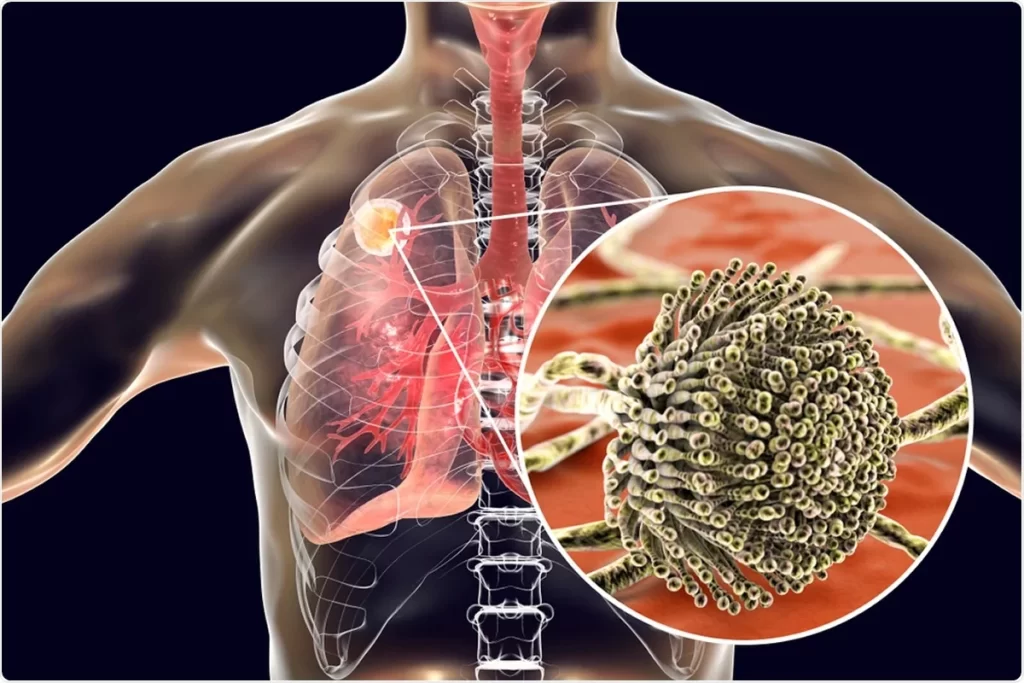

داء الرشاشيات العلاج و التشخيص في تركيا

كما يعرف داء الرشاشيات هو حالة يسببها العفن الرشاشيات. كما هناك عدة أنواع مختلفة من داء الرشاشيات يؤثر معظمها على الرئتين ويسبب صعوبات في التنفس.

أشكال داء الرشاشيات

قد تحدث الإصابة بداءُ الرَّشَّاشِيَّات بأشكال عدة: